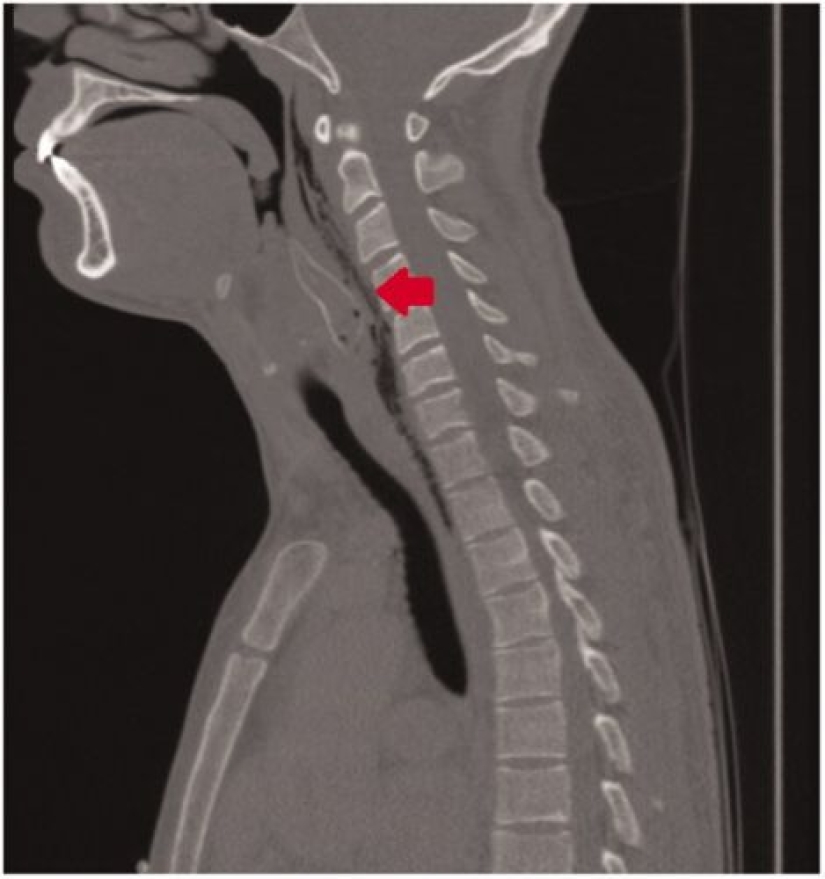

Un par de horas más tarde, cuando se probaron todos los métodos artesanales, los amigos llevaron al guasón a la clínica más cercana. El extraño paciente no quiso explicar a los médicos cuál era la razón de su difícil situación y simplemente se quejó de que se atragantaba con la comida. Pero la radiografía inmediatamente mostró que había un pez dentro del tipo y tuvo que admitir que había realizado un truco estúpido.

Los médicos lograron extraer el pescado muerto de la garganta del paciente, después de lo cual se le recetó un tratamiento de antibióticos de una semana de duración. El tipo se fue a casa, y los restos del pobre bagre, al Museo de Historia Natural de la ciudad de Rotterdam, donde todos pueden verlos.

¿Por qué surgió esta situación, que casi le cuesta la vida a un joven? Resulta que el bagre dorado de aspecto inofensivo (corydoras de bronce), en su hábitat natural, tiene una mala reputación entre los depredadores. Detrás de las aletas de estos peces hay puntas afiladas y duras, que, en caso de peligro, levantan rectas. Idealmente, esto debería evitar que un pez grande se traga a un bebé. Pero el hombre está dispuesto de manera algo diferente y las púas detuvieron al bagre donde ni él ni su víctima podían hacer nada.